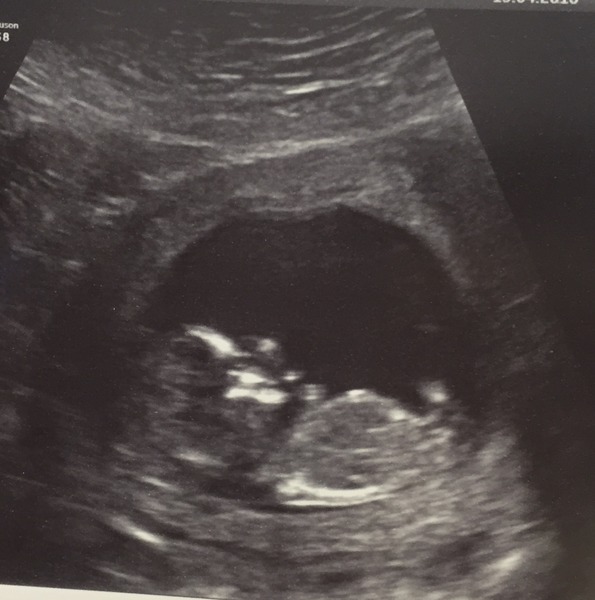

Lovely scans!!! Huge ThanksChocolateCake for you all!

Hello happy scan from my little bee too! We got a few royal waves Smile bub was lazy and liked being curled up even with some prodding but measurements look good at 1.4 now just waiting for blood test results.

Wonderful scan photos Lilian, Lara, Potato and Shelb! Glad all is well with your little ones.

Congratulations on all the happy scan news xxx

Ahh beautiful babies! Congratulations everyone!

Congratulations everyone for the scans, they're so lovely.

So happy to see all of the lovely scan pictures yesterday!